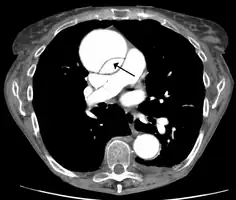

Computed tomography

Computed tomography angiography is a fast, noninvasive test that gives an accurate three-dimensional view of the aorta. These images are produced by taking rapid, thin-cut slices of the chest and abdomen, and combining them in the computer to create cross-sectional slices. To delineate the aorta to the accuracy necessary to make the proper diagnosis, an iodinated contrast material is injected into a peripheral vein. Contrast is injected and the scan performed using a bolus tracking method. This type of scan is timed to an injection to capture the contrast as it enters the aorta. The scan then follows the contrast as it flows through the vessel. It has a sensitivity of 96 to 100% and a specificity of 96 to 100%. Disadvantages include the need for iodinated contrast material and the inability to diagnose the site of the intimal tear.

Aortic dissection

CT with contrast demonstrating aneurysmal dilation and a dissection of the ascending aorta (type A Stanford)